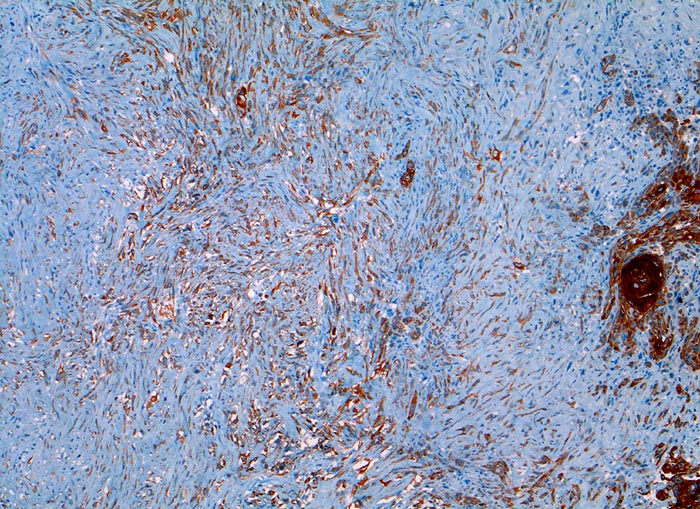

l/ Panzytokeratin (CK22/Lu-5)

Panzytokeratin (CK22/Lu-5)

Anfärbung:

Zytoplasma positiv.

Reaktion in Neoplasien:

Die meisten Karzinome und vereinzelte Sarkome reagieren positiv mit diesen Panzytokeratinen. CK22 ist etwas sensitiver und spezifischer als Lu-5. Entdifferenzierte oder sarkomatoide Karzinome können die Positivität für Zytokeratine verlieren.

Diagnostischer Nutzen:

Suchantikörper zur Abgrenzung von Karzinomen von Lymphomen, Sarkomen und malignen Melanomen. Identifikation von Karzinommikrometastasen in Lymphknoten.